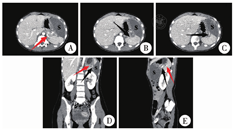

患儿,女,12岁3个月,因"左上腹痛9天余"于2021年11月23日入院。查体:左上腹饱满,可扪及大小约50 mm×100 mm×100 mm肿块,边界清晰,质韧,压痛明显,无反跳痛。超声于左上腹脾下方、左肾前方、胃底外侧探及-62 mm×49 mm×103 mm实质性低回声肿块,上缘与脾分界欠清楚,内可见少量血流信号。全腹CT平扫加增强见左上腹一梭形软组织密度肿块,大小约52 mm×103 mm×104 mm,内缘可见小斑片状稍高密度影,包膜完整,增强扫描见包膜强化,实质部轻度强化,内可见少许血管影,邻近的胃腔、胰腺及脾脏可见受压略移位(图1)。

注 A:脾动脉(红色箭头)从腹主动脉分出;B:脾动脉于脾门处分出细小血管支(黑色箭头); C:血管支延伸至肿物(s)边缘截止,末端扭曲增粗;D:脾动脉与血管分支关系冠状图;E:脾动脉与血管分支关系矢状图

副脾扭转常位于副脾蒂。有学者认为可通过B超寻找扭转的副脾蒂进行早期诊断,因为副脾扭转后副脾蒂内血流在B超中会形成典型的"漩涡征",副脾蒂也会扭转成"麻花状"[8]。但腹腔环境复杂,临床医师常难以捕捉到典型征象,副脾扭转临床误诊率较高。副脾常由脾动脉分支供血,结合既往病例,我们认为可在增强CT成像上顺脾动脉分支向远端追踪。由于副脾扭转会导致脾动脉分支内血流中断或减少,增强CT上可寻及一条细长的高信号血管影从脾动脉分出,并延伸至肿物边缘,即副脾的供血分支,其末端常因血管扭曲致显像稍增粗。同时由于扭转后侧支循环建立,肿物的包膜也会被略微强化(图1),再结合肿物位置及形态即可诊断。当然,增强MRI亦可清晰显示扭转血管,且与增强CT相比,增强MRI对出血像更加敏感[9]。但增强MRI临床操作周期较长,易延误病情。